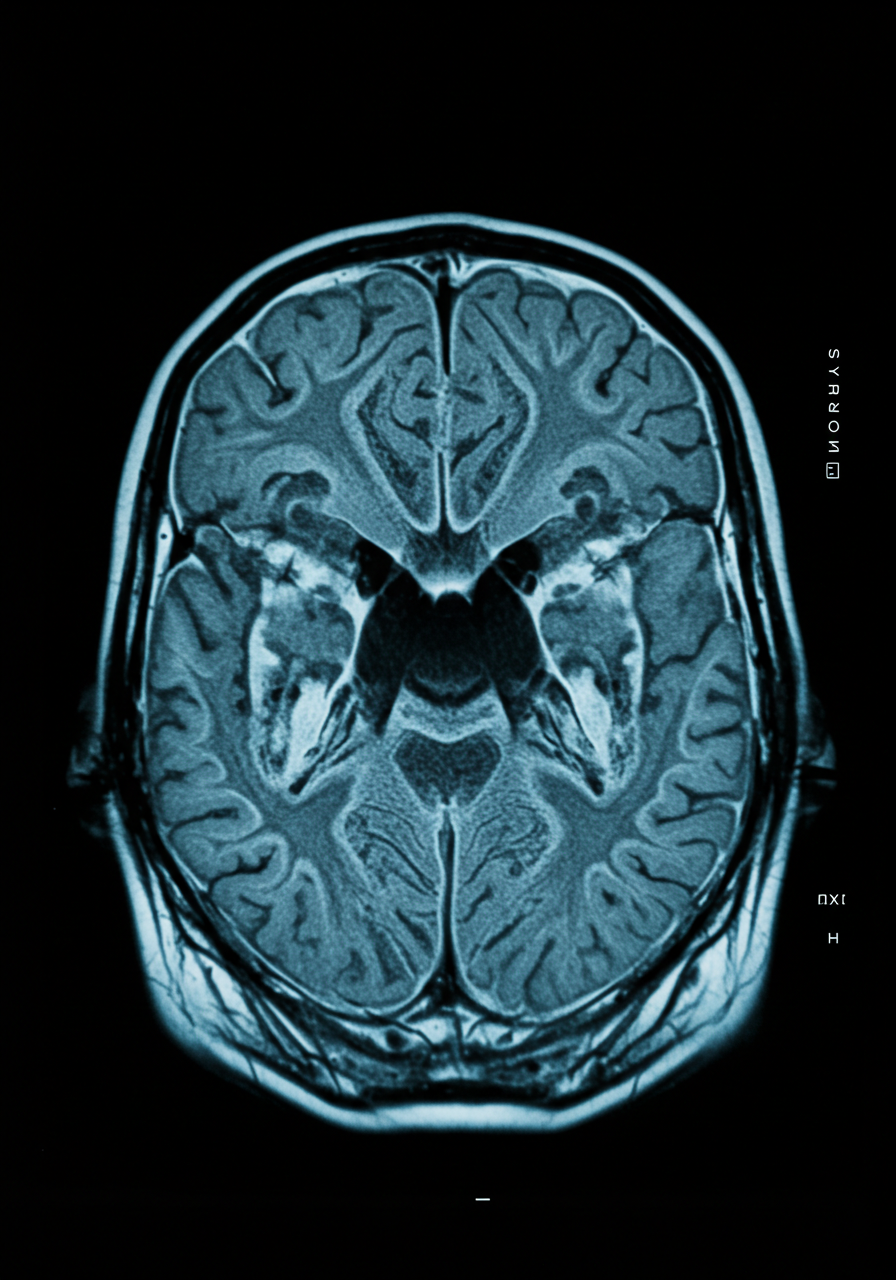

최근 두개골의 빠른 노화 측정이 MRI 기술을 통해 가능해졌습니다. 이러한 발전은 치매와 같은 신경퇴행성 질환의 예측 가능성을 높이는 데 기여하고 있습니다. 두개골의 구조적 변화는 인지 기능 저하와 밀접한 관련이 있으며, 이를 통해 조기에 경고 신호를 포착할 수 있습니다. 본문에서는 두개골의 빠른 노화 측정과 치매 예측 가능성에 대한 핵심 내용을 정리했습니다. 지금부터 이와 관련된 주요 정보들을 하나씩 살펴보겠습니다.

과학자들은 MRI를 통해 두개골의 노화 과정을 정밀하게 분석할 수 있게 되었습니다. MRI 기술은 비침습적으로 두개골의 상태를 평가할 수 있는 장점이 있습니다. 이를 통해 연구자들은 노화가 진행되는 방식과 그에 따른 뇌의 변화를 관찰할 수 있습니다.

MRI(자기공명영상)는 강력한 자기장과 전파를 이용하여 인체 내부의 구조를 촬영하는 기술입니다. 이 기술은 방사선이 아닌 자기장을 사용하여 안전하게 이미지를 생성합니다. MRI는 특히 연부 조직을 잘 보여주기 때문에 뇌와 두개골 구조를 분석하는 데 유용합니다.

MRI의 해상도는 매우 높아, 두개골의 미세한 변화도 감지할 수 있습니다. 이러한 기술적 발전은 두개골의 노화 과정을 보다 정밀하게 분석할 수 있는 기회를 제공합니다. 연구자들은 이 데이터를 바탕으로 치매와 같은 질환의 조기 예측 모델을 개발하고 있습니다.

두개골 MRI는 다양한 분야에서 활용됩니다. 노화 연구뿐만 아니라 사고나 질병으로 인한 손상을 평가하는 데에도 효과적입니다. 특히, 치매 환자들의 두개골 변화를 비교 분석함으로써 질환 진행 상황을 모니터링할 수 있습니다.

최근 연구에 따르면, 두개골 MRI를 통해 인지 기능 저하의 조기 징후를 포착할 수 있는 가능성이 높아졌습니다. 이러한 조기 발견은 치료 방법을 조정하고, 환자의 삶의 질을 개선하는 데 도움이 됩니다.